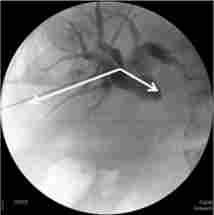

Як правило, операція закінчується зовнішньо-внутрішнім дренуванням протоки підшлункової залози (рис. 28.9).

Зовнішньо-внутрішнє дренування протоки підшлункової залози (контрастна нанкреатографія)

Мал. 28.9. Зовнішньо-внутрішнє дренування протоки підшлункової залози (контрастна нанкреатографія):